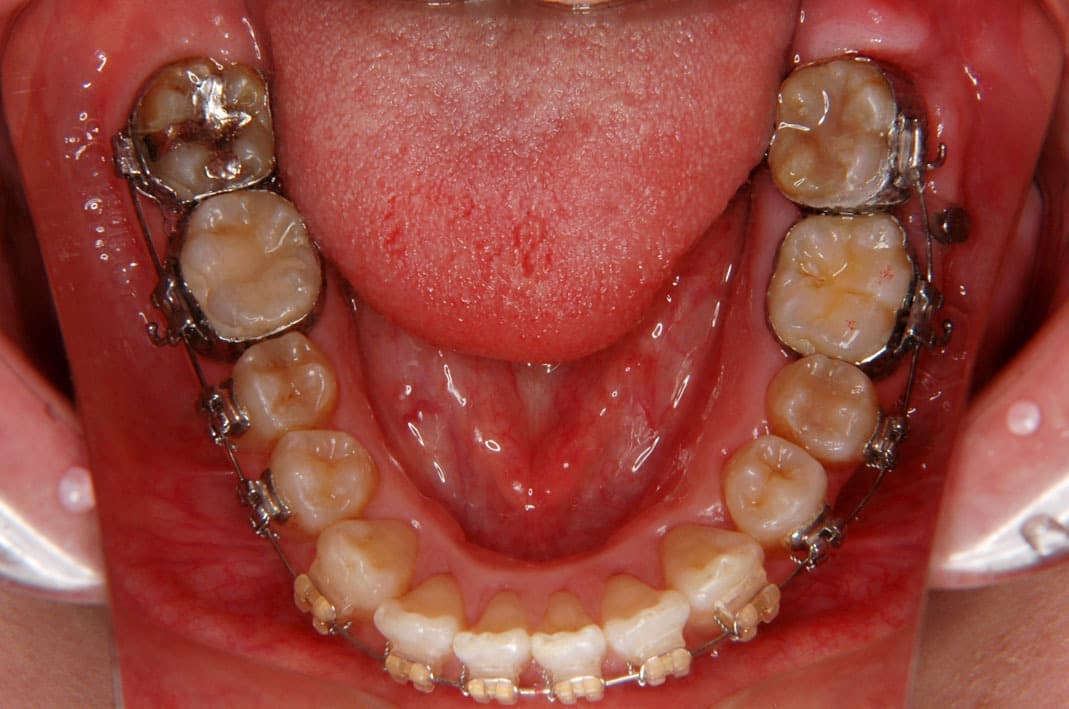

歯科矯正用アンカースクリューの使用例

例1)